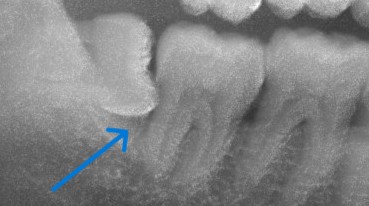

レントゲンでは、親知らずが手前の歯の根元にぶつかり、

その部分が黒く写っていました。虫歯が疑われる状態です。

抜歯後のレントゲンでも、やはり根元に虫歯が残っているのが分かります。

治療直後のレントゲン写真

白く写っている部分が、レジンを詰めたところです。

必要な部分だけを最小限に削り、しっかり封鎖されています。